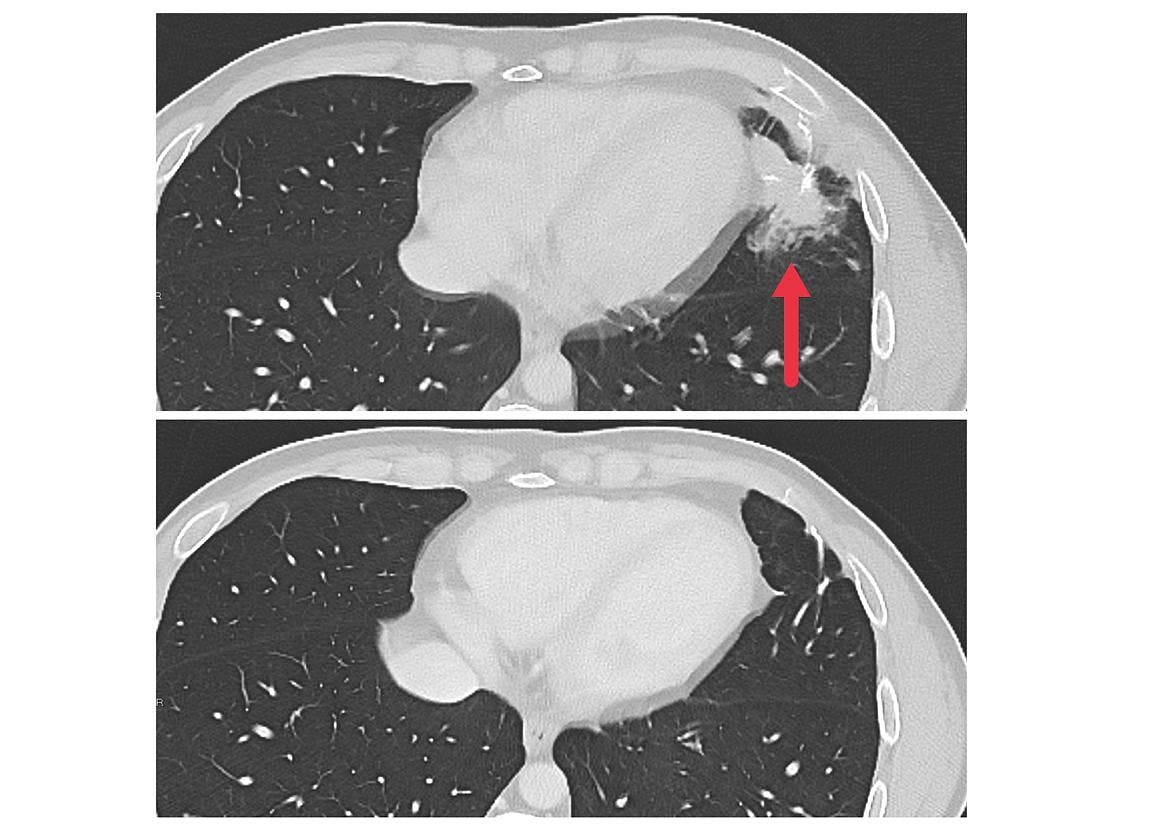

As part of a larger phase 2 trial, seven patients with metastatic colon cancer were treated with the experimental personalized cellular immunotherapy. All seven received several doses of the immunotherapy drug pembrolizumab (Keytruda) before the cell therapy and another immunotherapy drug called IL-2 afterward. Three patients had substantial shrinkage of metastatic tumors in the liver, lung, and lymph nodes that lasted for four to seven months. The median time to disease progression was 4.6 months.